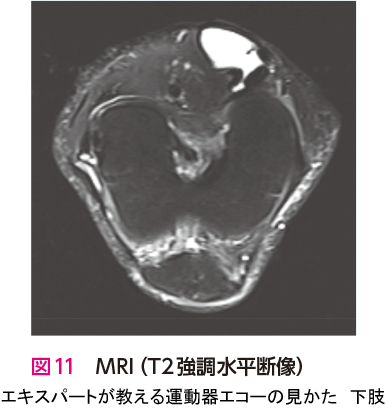

人工関節置換術を施行した症例です.エコー検査での膝関節前方(長軸像)では,膝蓋骨の骨棘と関節水腫を観察できます.また,膝関節内側(長軸像)では,内側側副靭帯浅層の直下に骨棘と内側半月板を観察できます.骨棘は大腿骨と脛骨から大きく張り出しています(図1🅑*).